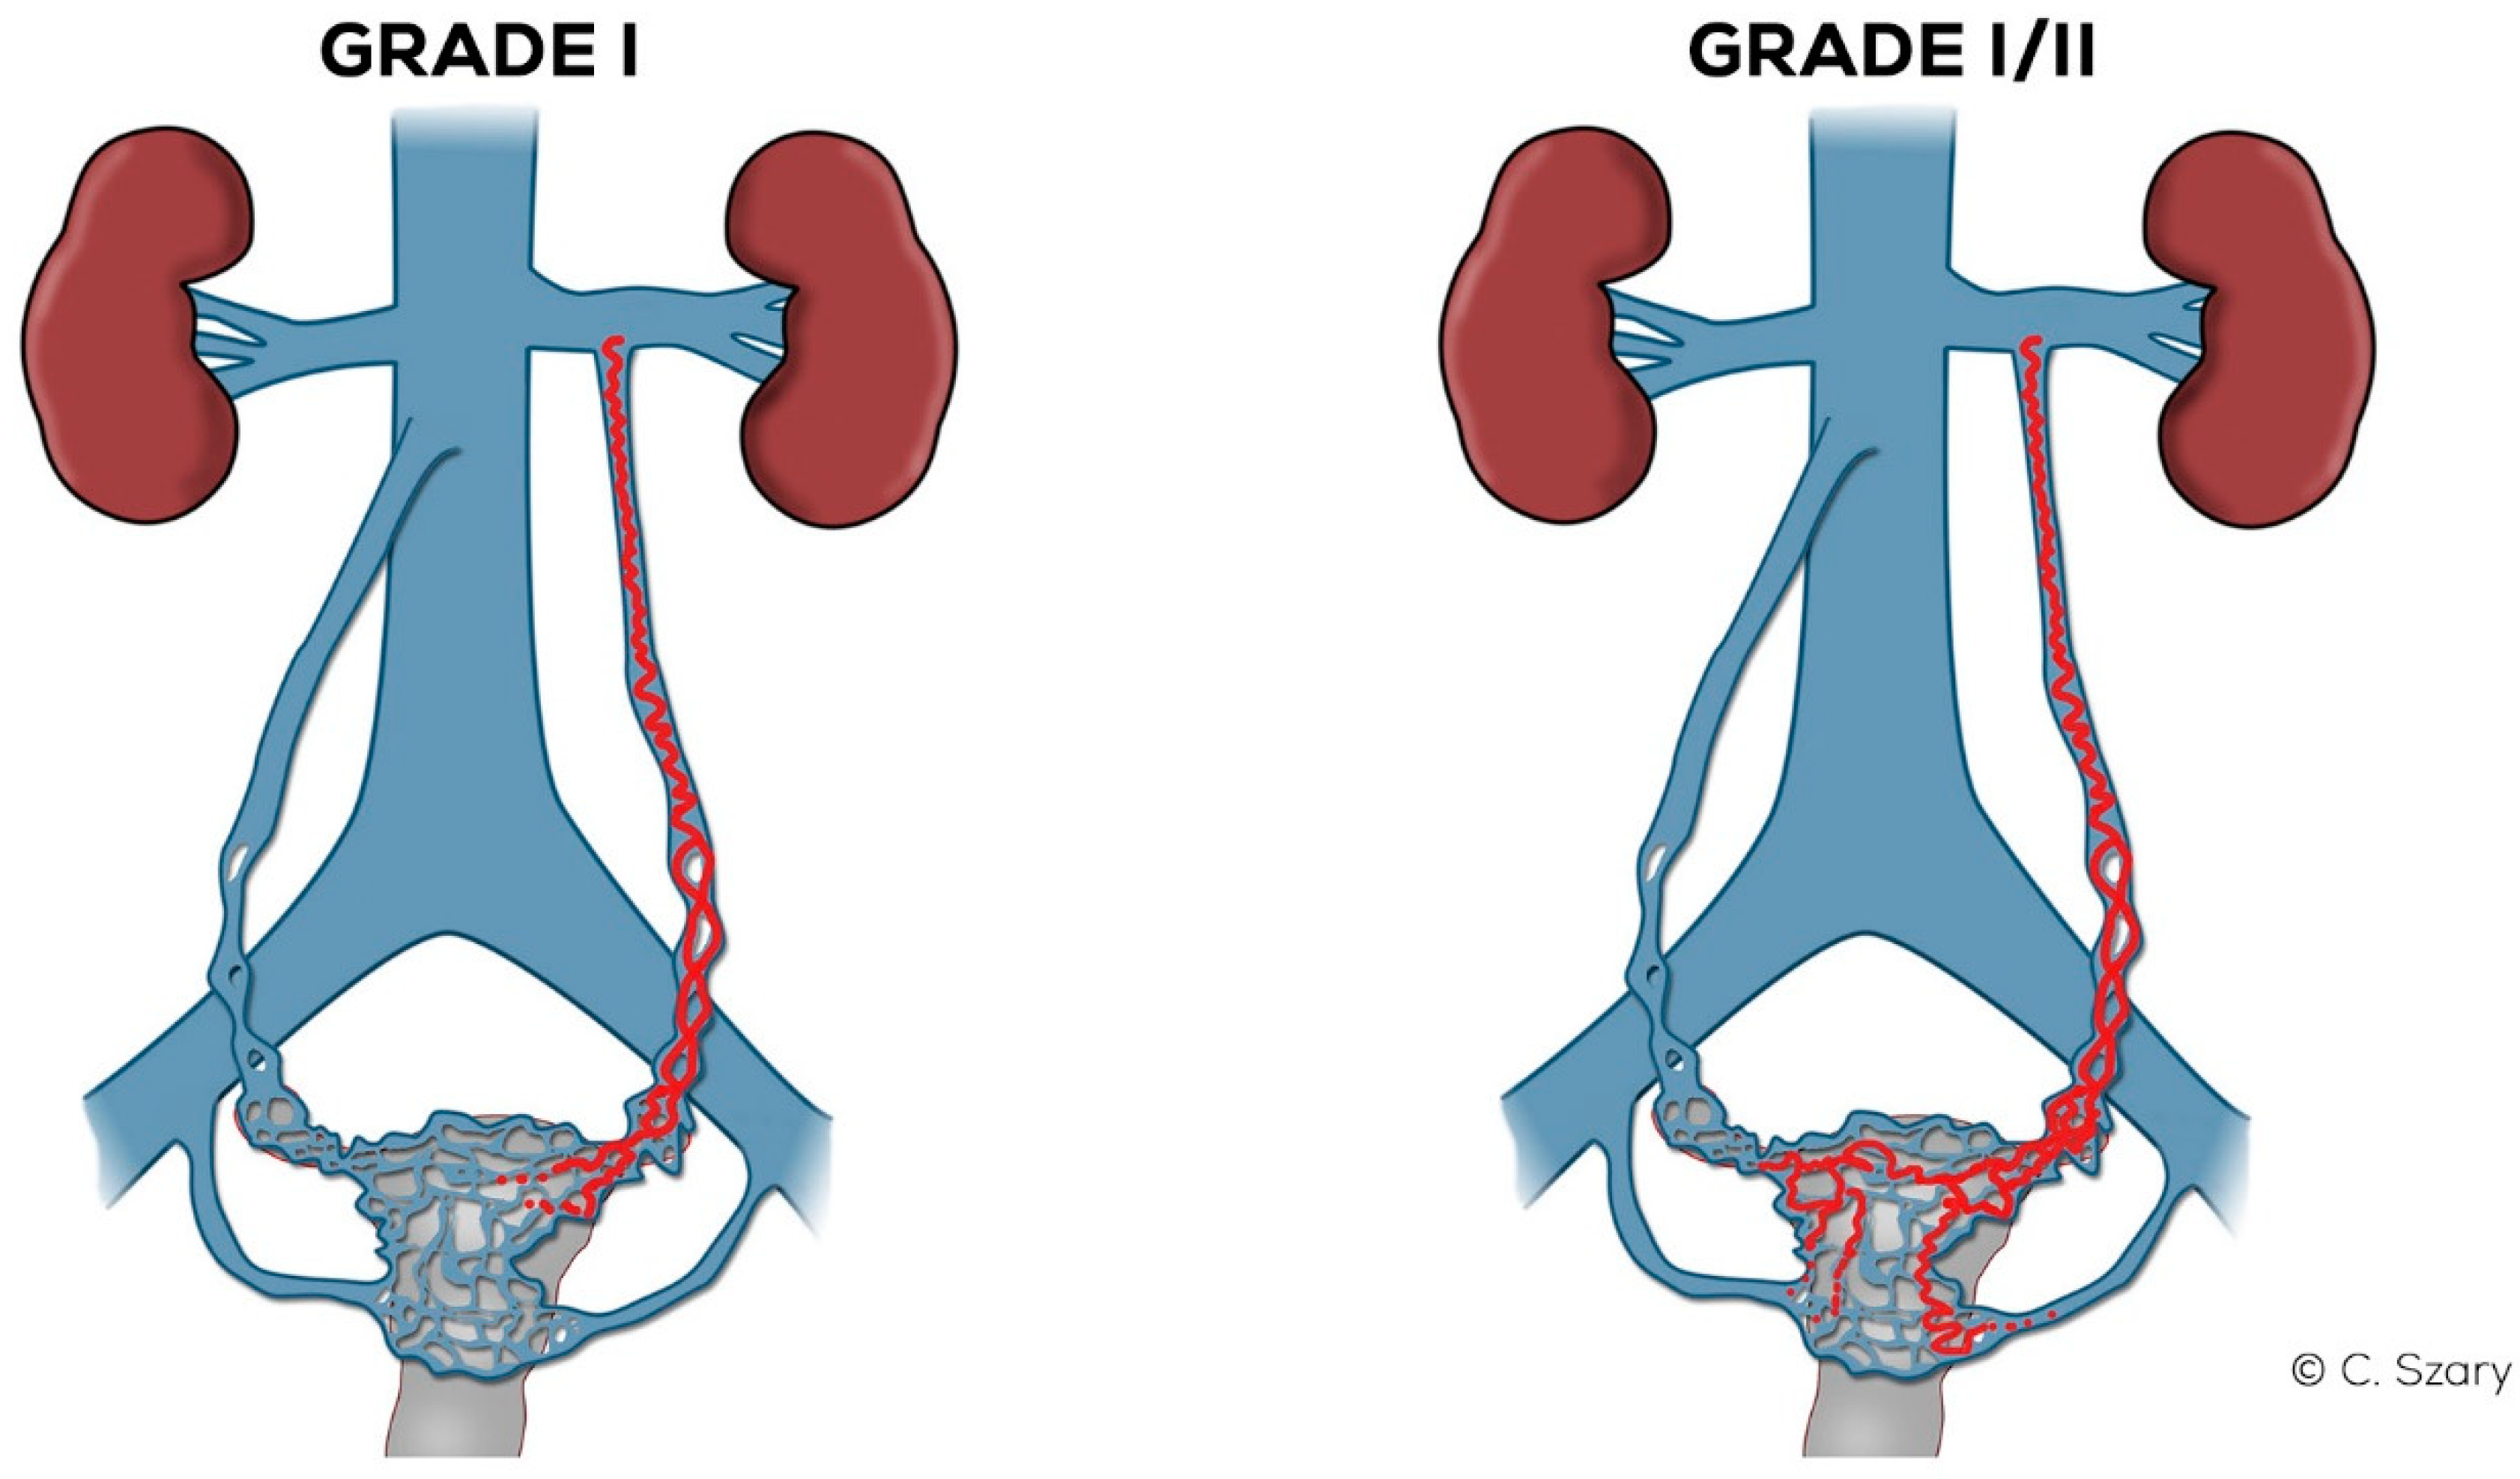

Figure 8.

Schematic illustration of ovarian veins insufficiency: Grade I (GI) and Grade I/II (GI/II).

4.2.2. Grade I/II (GI/II)

In the Grade I/II (Figure 8), the LOV trunk is insufficient with relatively little dilatation (mean diameter about 6–6.5 mm). In the case of GI/II insufficiency, the LOV trunk ostium is usually slightly dilated. The distension of the venous plexuses is slight and affects the left side exclusively (lPUV up to 5.5 mm). In the GI/II, there is a mild volumetric overload of the LIILV drainage with bLIILV dilation to 5–6 mm. The right side does not show typical features of overload and insufficiency. Both the ROV trunk and its runoff do not show any signs of excessive distension. There is also no dilation of RIILV trunk and its branches (Figure 10).